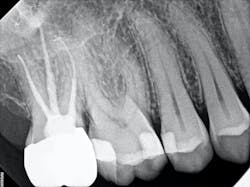

In the case below, tooth No. 2 was diagnosed with symptomatic irreversible pulpitis and symptomatic apical periodontitis with a mesial marginal ridge fracture due to extensive caries (figure 1). Root canal therapy and a full coverage crown were recommended and the patient accepted.

The carious tissue was removed, followed by the endodontic procedure and subsequent placement of the build-up. Despite the deep extent of mesial decay, a clear and accurate scan was achieved (figure 2).

The iTero scanner was able to clearly define the delineation between the soft and hard tissue as can be seen in this image of the digital die trim (figure 3). Radiographs were captured on delivery revealing a clinically acceptable outcome for the patient (figure 4). Direct restorations were completed on teeth Nos. 3 and 4 during this visit.